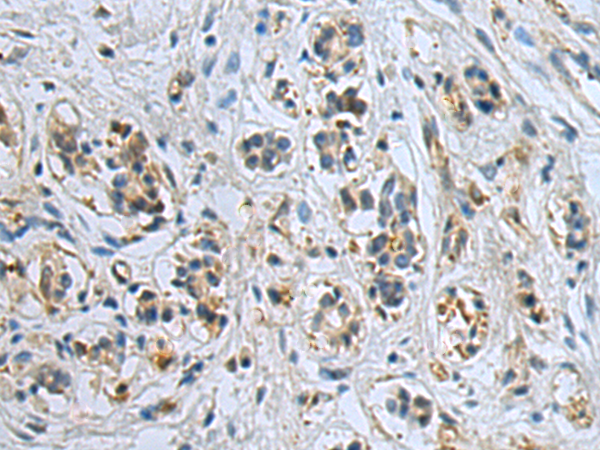

分类: 科研抗体货号: P07155别名: MN; CAIX应用: WB,IHC反应种属: Human